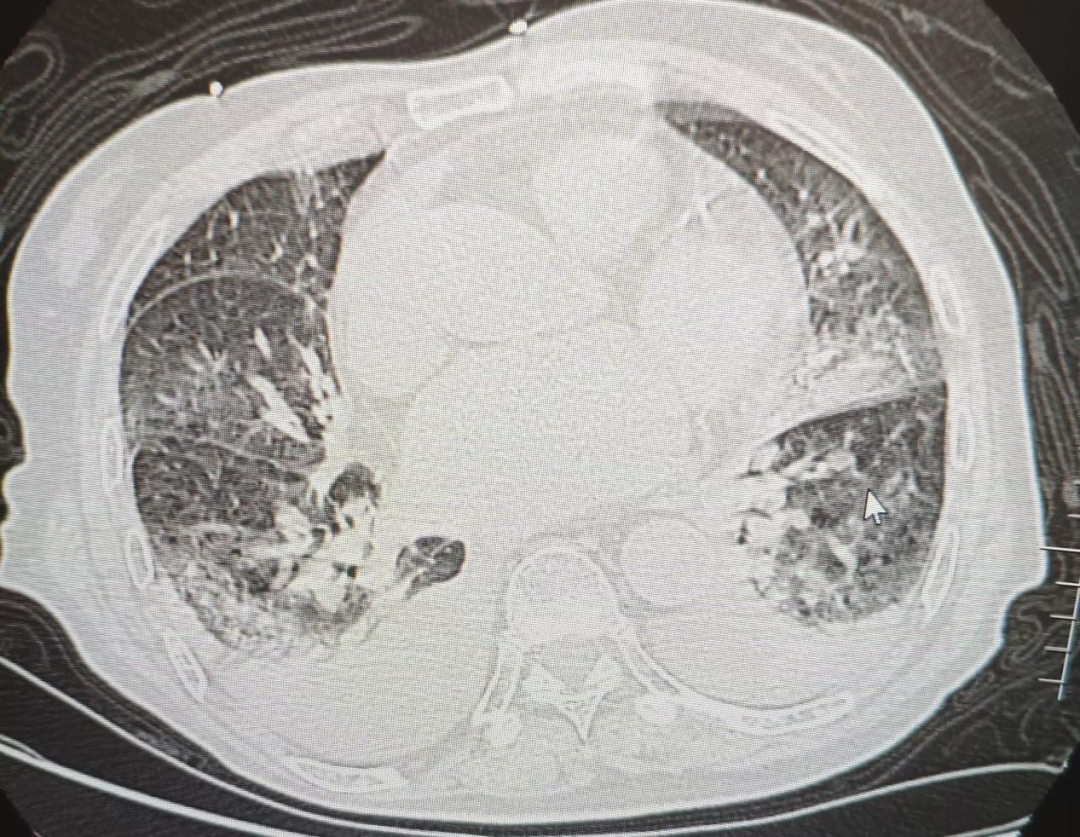

速看!流感暗箭——解码隐匿的致命连击

感染性疾病科 上饶市人民医院